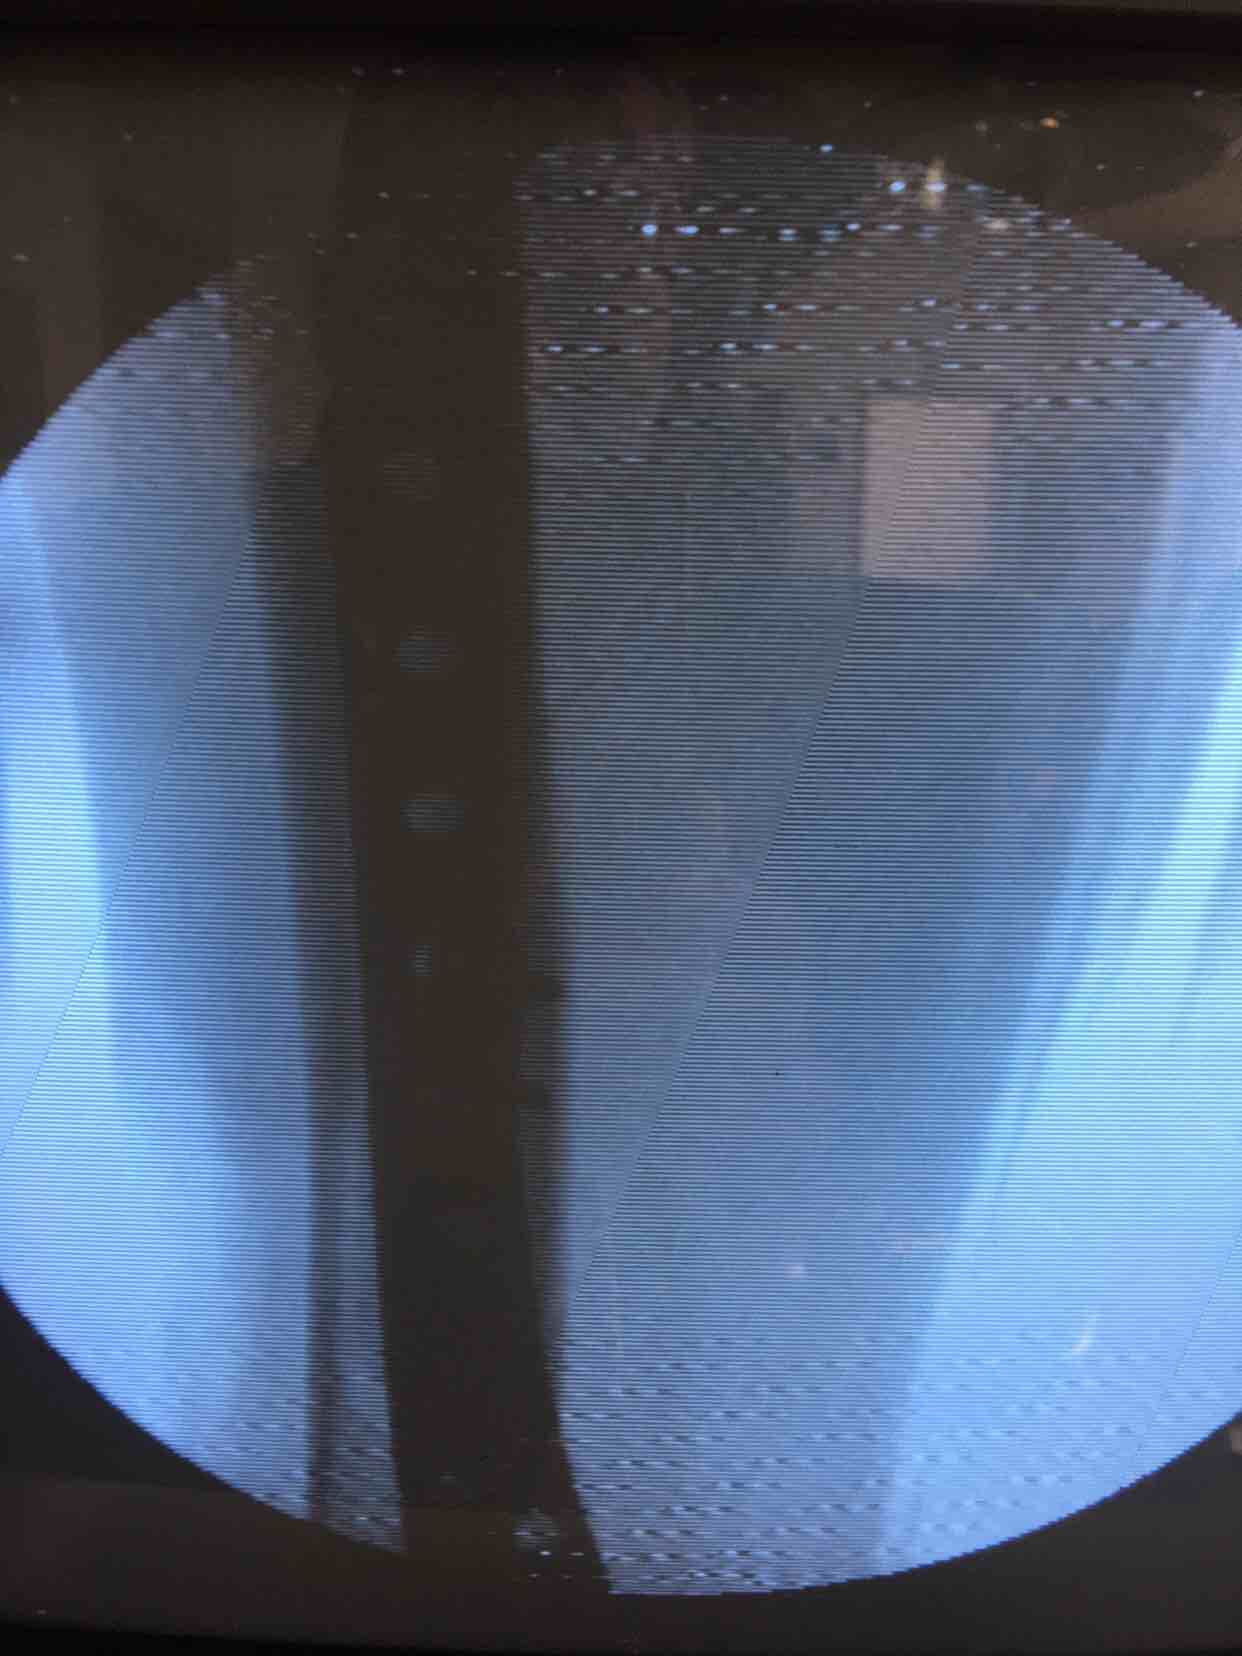

胫腓骨粉碎性骨折(微创手术)

骨折 腓骨粉碎性骨折 胫腓骨粉碎性骨折

诊断右胫腓骨粉碎性骨折完善术前检查,消肿后在腰麻下行切复内固定术,术后抗炎,消肿等处理。